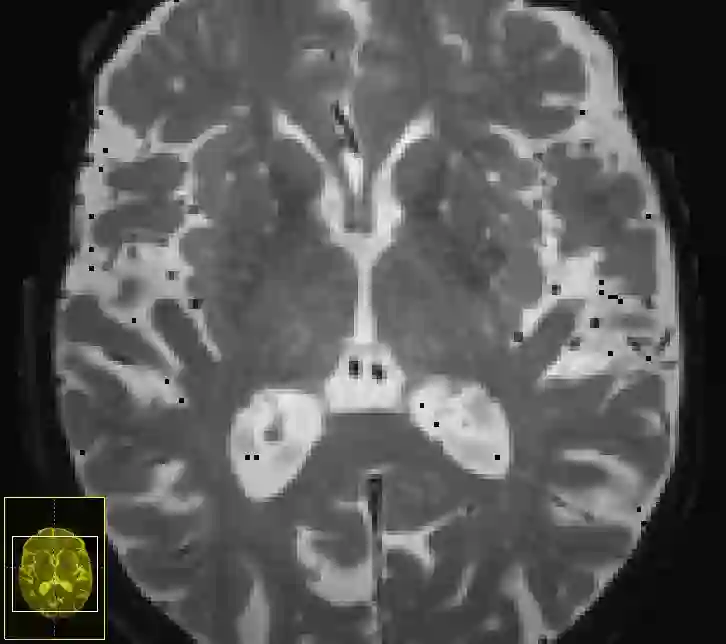

Imaging markers of cerebral small vessel disease provide valuable information on brain health, but their manual assessment is time-consuming and hampered by substantial intra- and interrater variability. Automated rating may benefit biomedical research, as well as clinical assessment, but diagnostic reliability of existing algorithms is unknown. Here, we present the results of the \textit{VAscular Lesions DetectiOn and Segmentation} (\textit{Where is VALDO?}) challenge that was run as a satellite event at the international conference on Medical Image Computing and Computer Aided Intervention (MICCAI) 2021. This challenge aimed to promote the development of methods for automated detection and segmentation of small and sparse imaging markers of cerebral small vessel disease, namely enlarged perivascular spaces (EPVS) (Task 1), cerebral microbleeds (Task 2) and lacunes of presumed vascular origin (Task 3) while leveraging weak and noisy labels. Overall, 12 teams participated in the challenge proposing solutions for one or more tasks (4 for Task 1 - EPVS, 9 for Task 2 - Microbleeds and 6 for Task 3 - Lacunes). Multi-cohort data was used in both training and evaluation. Results showed a large variability in performance both across teams and across tasks, with promising results notably for Task 1 - EPVS and Task 2 - Microbleeds and not practically useful results yet for Task 3 - Lacunes. It also highlighted the performance inconsistency across cases that may deter use at an individual level, while still proving useful at a population level.